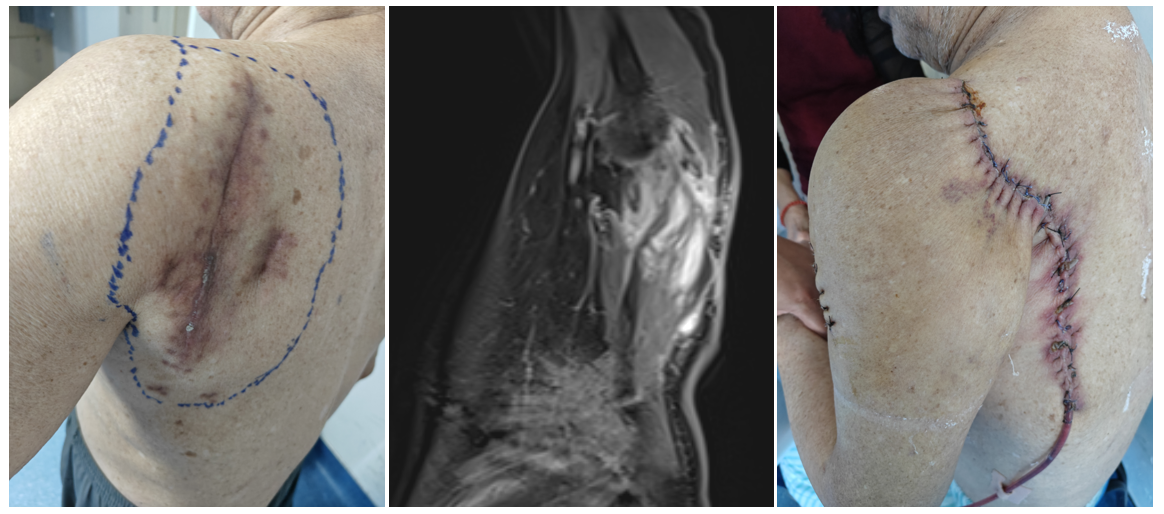

案例一 左上臂粘液纤维肉瘤(术后复发),行肿瘤扩大性切除,使用带血管蒂的背阔肌皮瓣转移作软组织修复。

案例二 左肩胛区粘液纤维肉瘤(术后复发),转诊我院,在肩胛带全切除后进行屈肘功能重建手术。